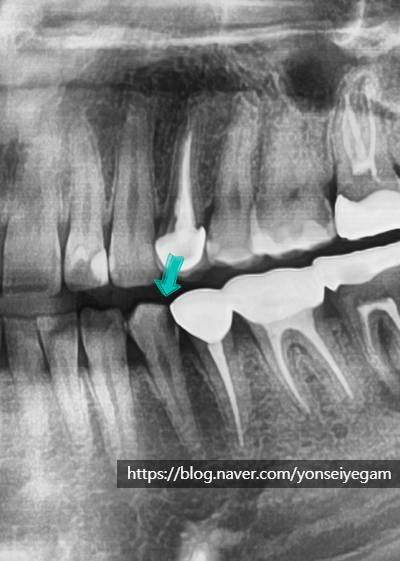

2년후 2021년, 환자분이 치아에 구멍이 났다며 오셨습니다. 엑스레이 상에는 다음과 같이 나타났습니다.

2년전 엑스레이 보다 까맣게 보이는 부분이 훨씬 커지고 치아 중간에 있는 치아신경과 근접해 진 것을 볼 수 있습니다. 실제로 보이는 모습은 아래 사진과 같았습니다.